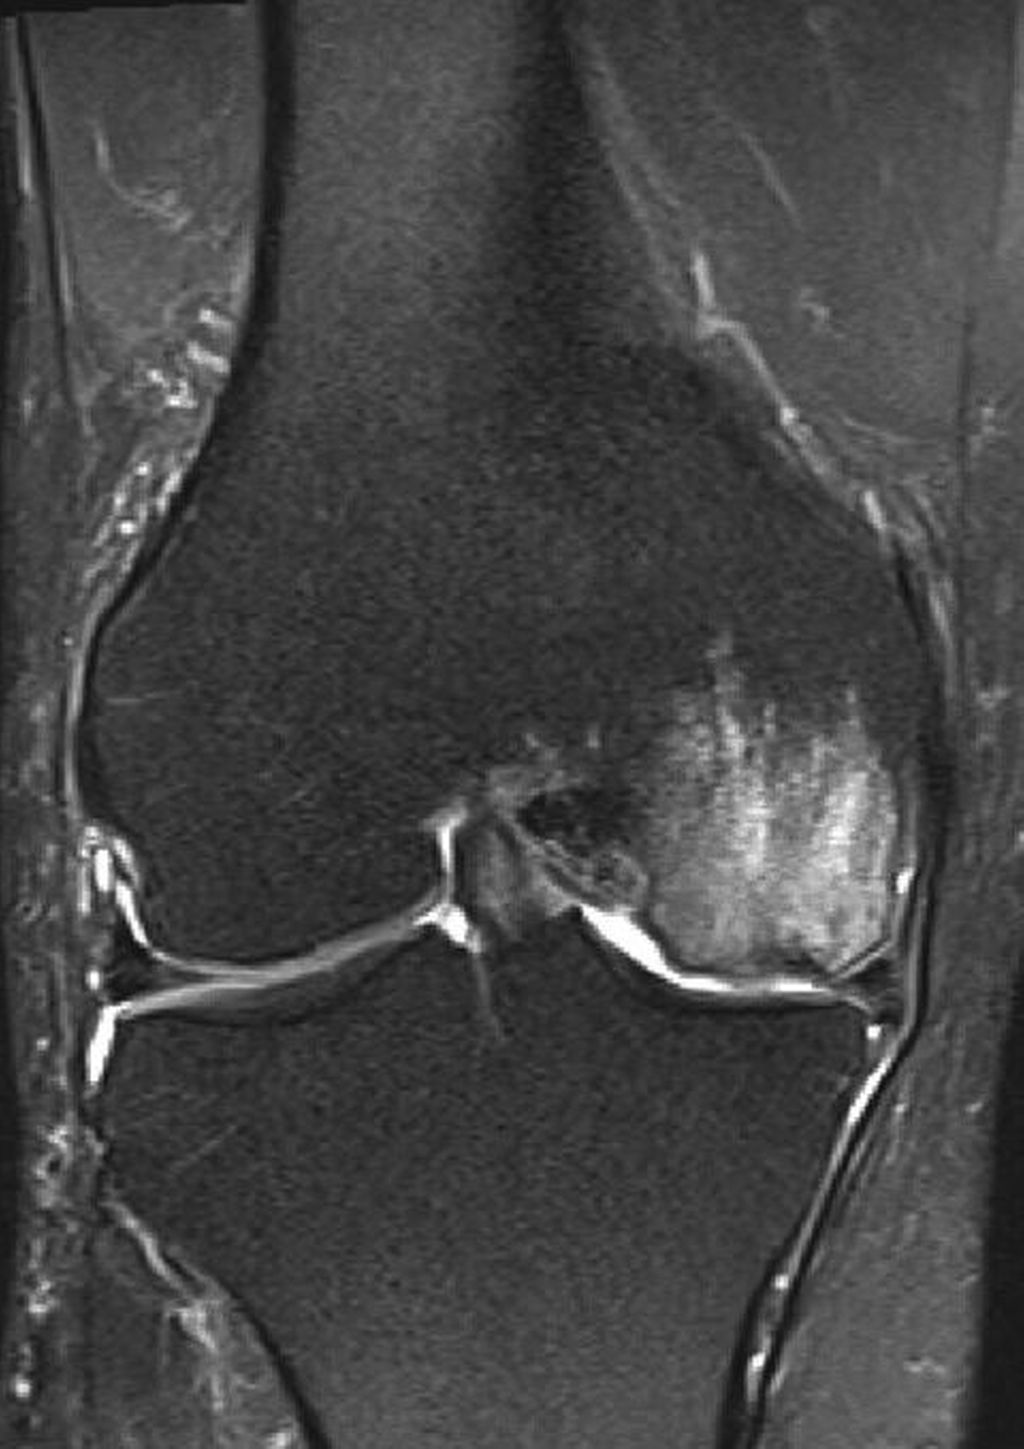

Relevanz der Beinachse bei der Therapie von degenerativen Meniskusläsionen